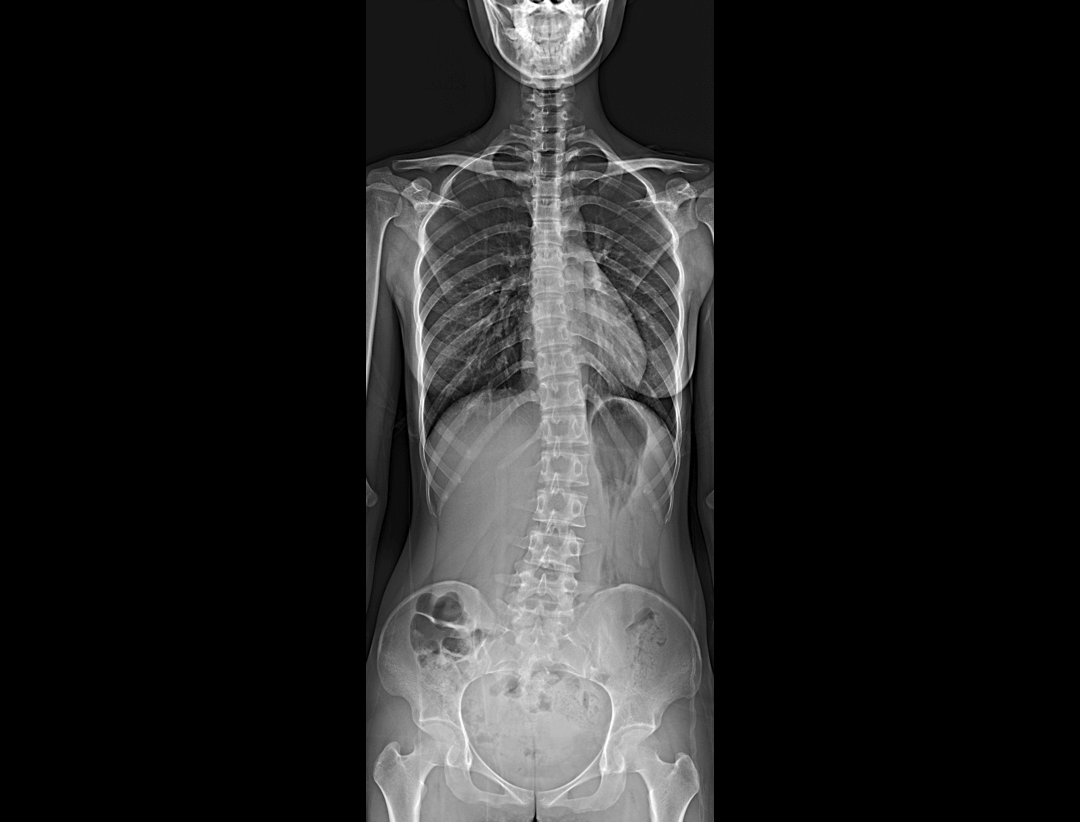

支持自动立位及卧位无尺全景拼接,为骨科、整形外科提供高质量全景影像。

集成脊柱Cobb角及股骨颈干角测量功能,精准指导外科手术及术后评估。

全脊柱正位、侧位

腰椎正位、侧位